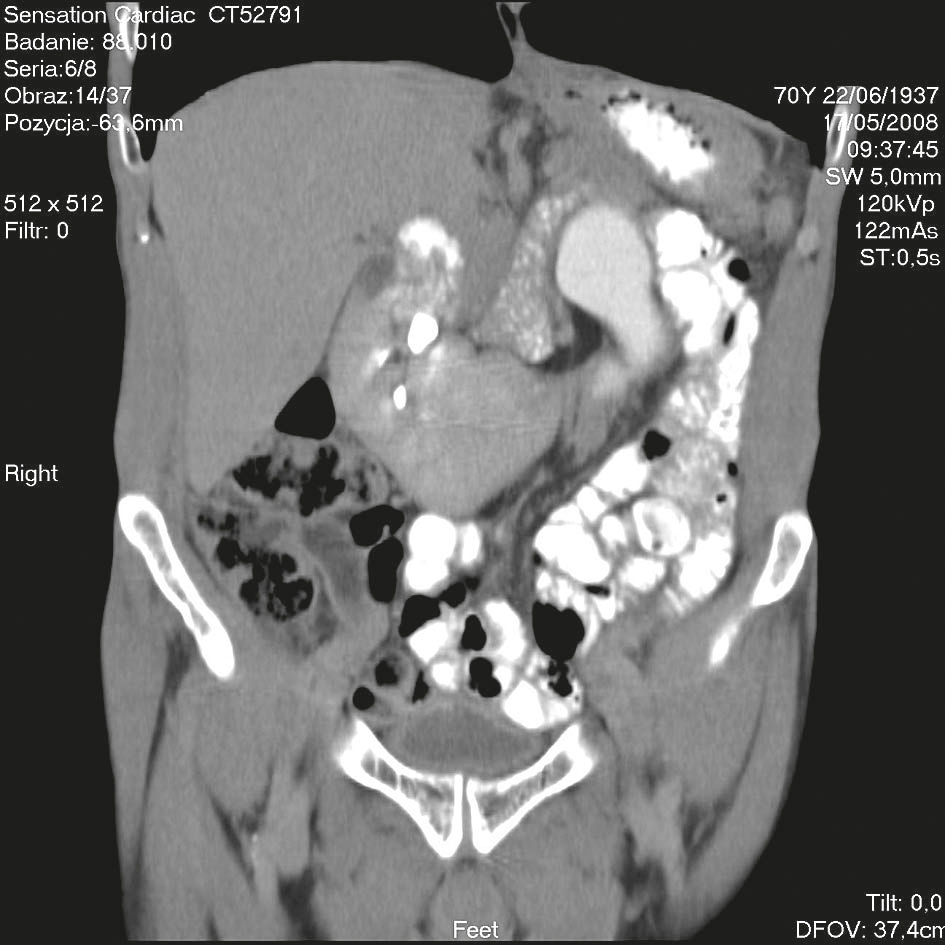

Tomografia komputerowa – nerka podkowiasta z lewostronnym wodonerczem

W pracy przedstawiono pacjenta z nerką podkowiastą, u którego pierwotny guz moczowodu doprowadził do powstania wodonercza.